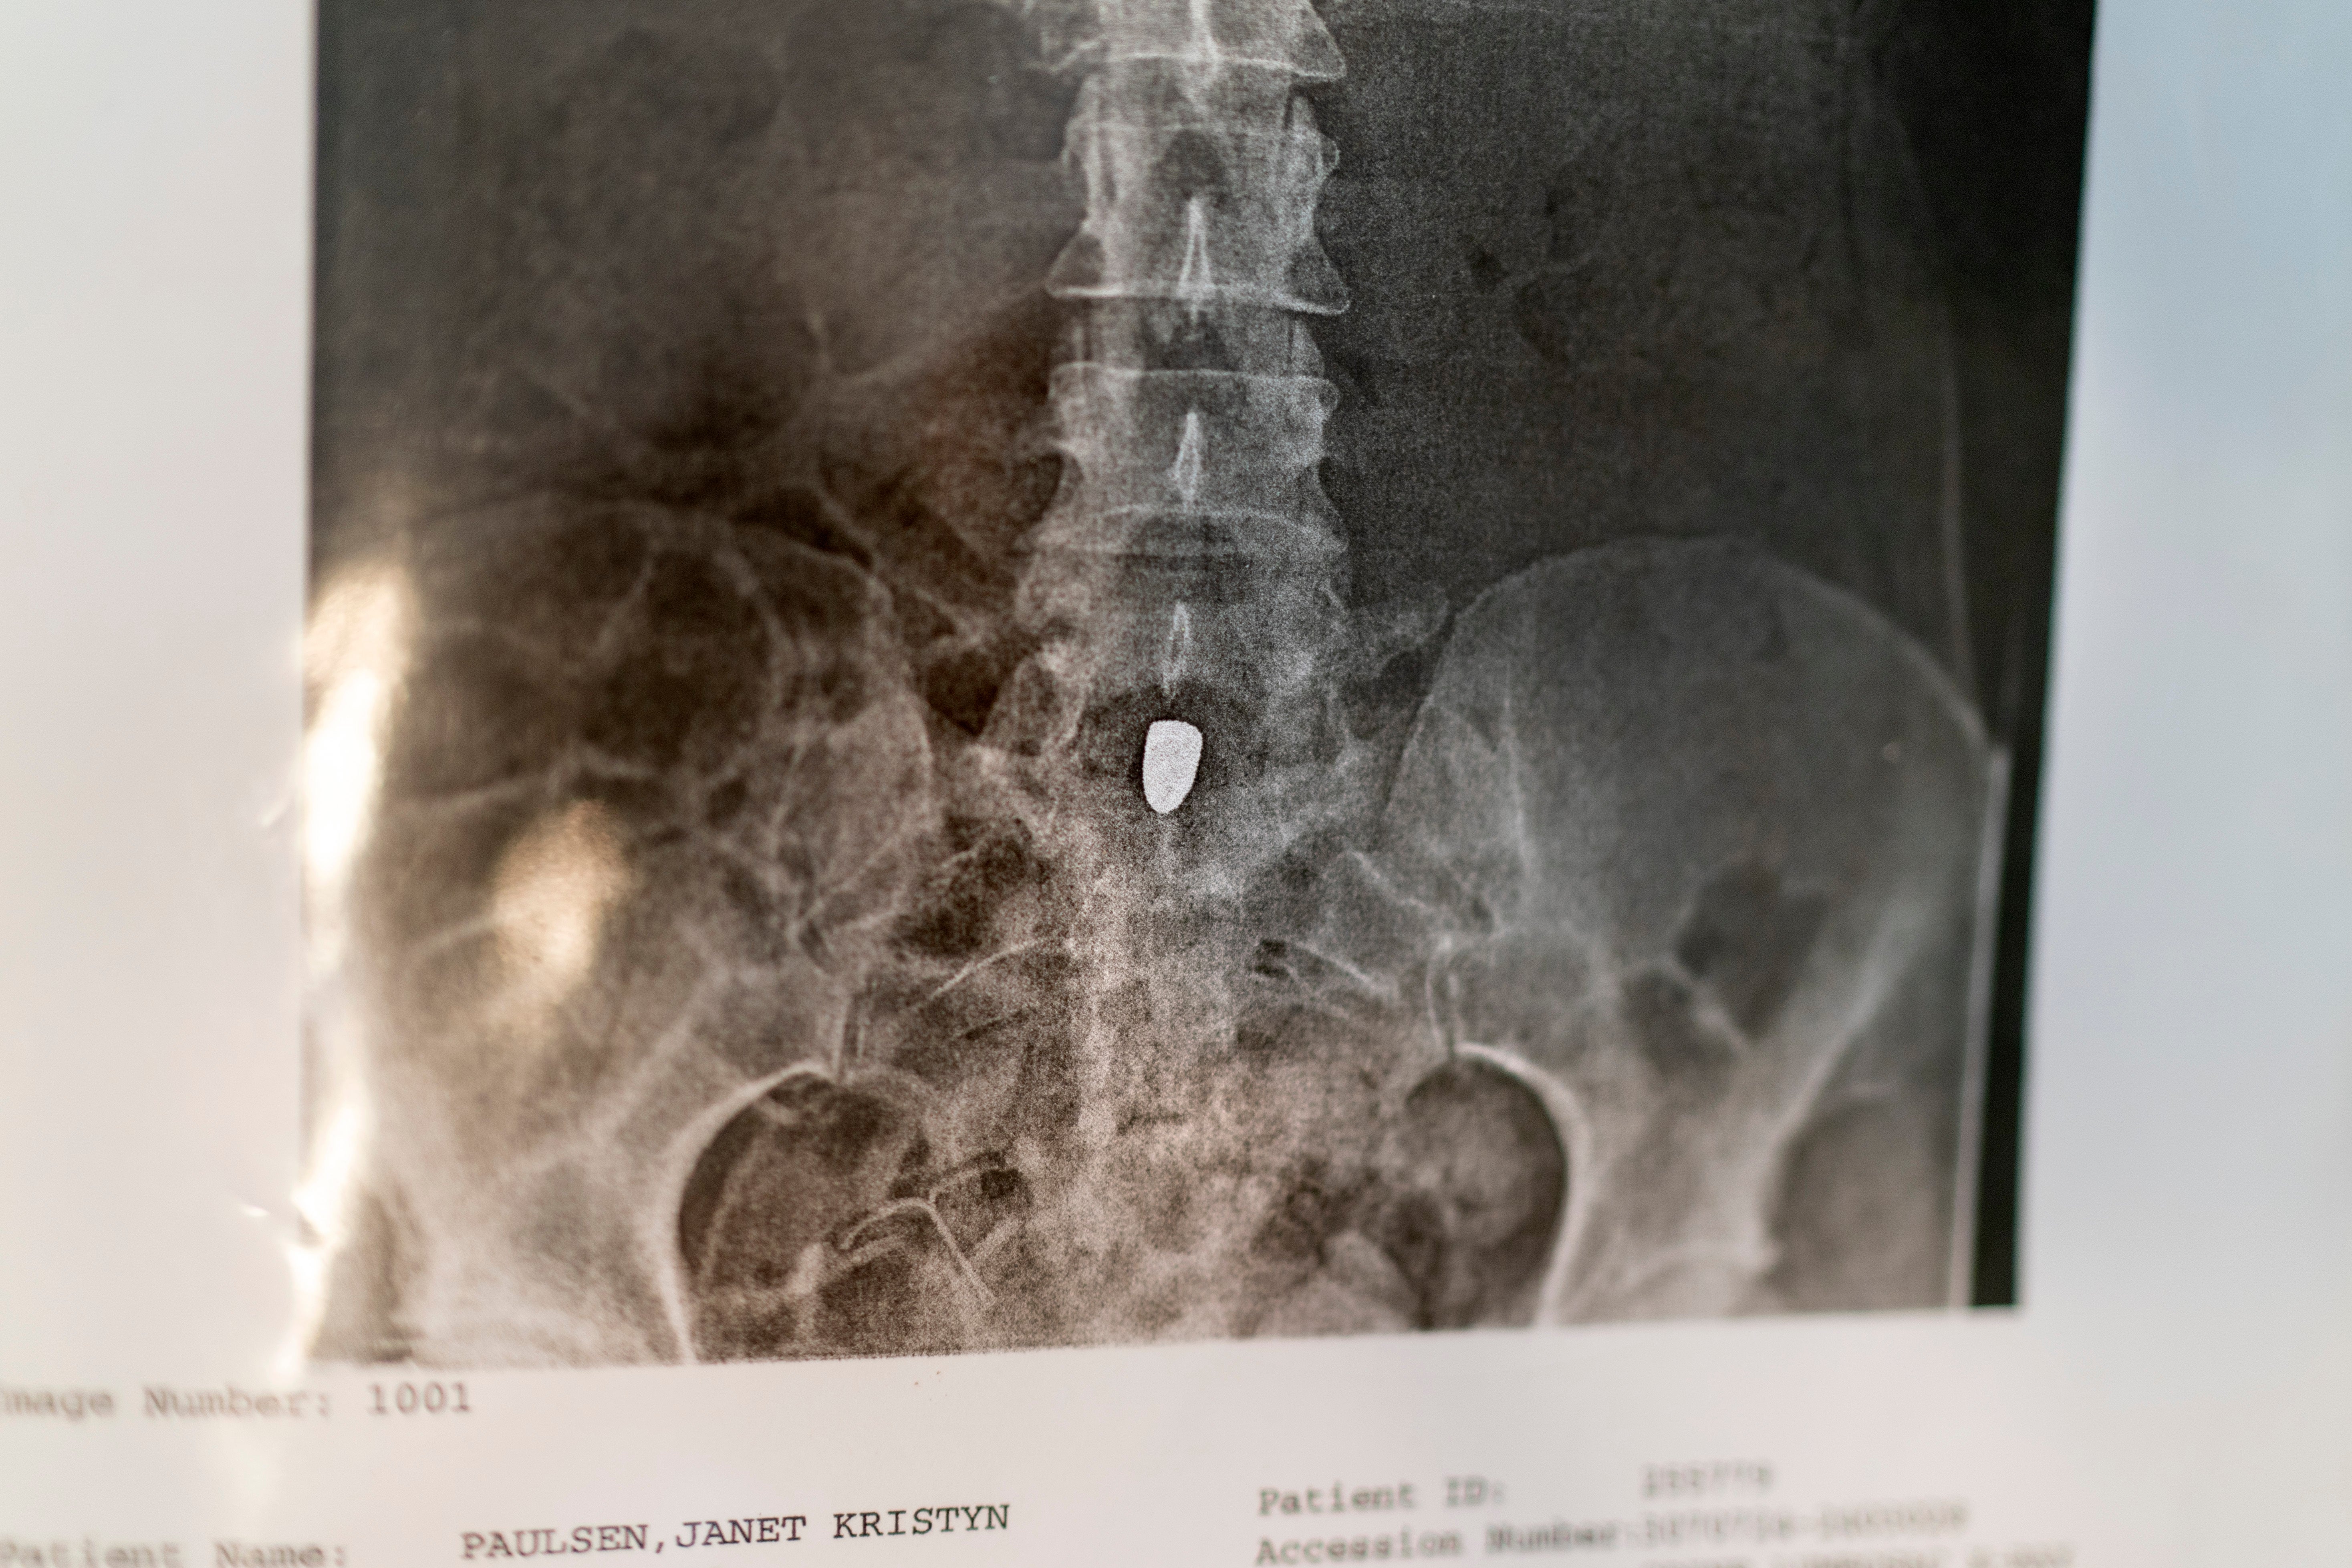

Five days later, Bland ambushed Paulsen in the garage as she stopped home with groceries. He used the 9 mm semiautomatic pistol to shoot her six times, as she tried to flee, before killing himself.

“It took me five years to get up the courage to divorce him, because I knew I would pay a price. And you know what happened when I did? He shot me,” said Paulsen, 53, a former property manager and endurance athlete who was left partially paralyzed in the 2015 shooting.

Her medical care has since cost about $2.5 million, much of it borne by society at large through health insurance payments.